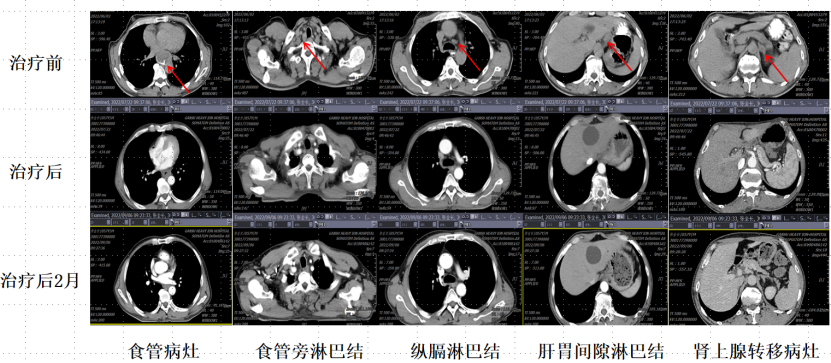

病例一:患者,张xx,男性,60岁,江苏徐州籍。确诊食管癌3月余。2022-02 患者于徐州市肿瘤医院行胸部CT提示:食管胸下段占位性病变。胃镜示:食管下段新生物;病检示:鳞状细胞癌。给予2周期“卡铂+白蛋白紫杉醇”治疗。无明效效果, 2022-04 患者复查胃镜示:距门齿约25cm起始至贲门见不规则粘膜隆起,质硬,触之易出血,管腔狭窄。2022-05 患者行PET-CT示:1.食管中下段原发病灶糖代谢明显增高;右上纵隔气管旁及肝胃间隙多发增大淋巴结,代谢中度增高,考虑转移;左侧肾上腺结节灶,代谢明显增高,考虑转移。颈部腹部多发淋巴结转移。食管中下段鳞状细胞癌(隆起型):多发淋巴结转移,左侧肾上腺转移,左侧甲状腺转移      cT4N2M1 IV期 KPS评分:70分 ECOG评分:2分。2022-05-20 患者仅能进食半流质食物,感全身乏力,就诊于我院行进一步治疗。重离子治疗期间,体重增加了10公斤。

本例非常晚期的食管癌,采用重离子广泛治疗后,效果良好,长期生存。肿瘤消失,体力状况良好。